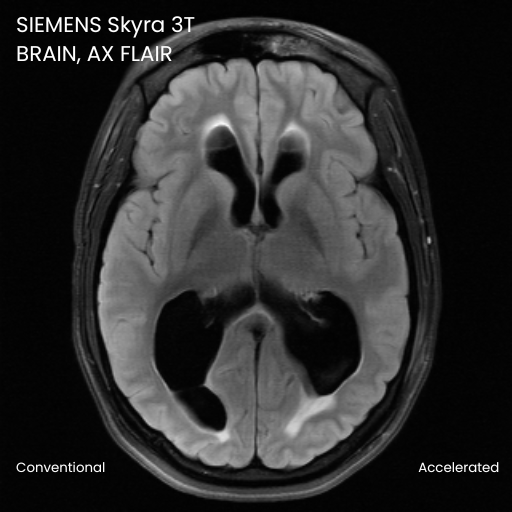

Case Studies

Robarts Research Institute

The evaluation of the effectiveness of DeepFoqus-AccelerateTM for accelerated brain MRI scans.

Accept up to 4x accelerated scans and reconstruct them to yield acceptable scans when compared to standard unaccelerated scans.

*The claim is based on the prospective studies we conducted with radiologists. Results in other cases may vary.14.0 min and 49.02 sec